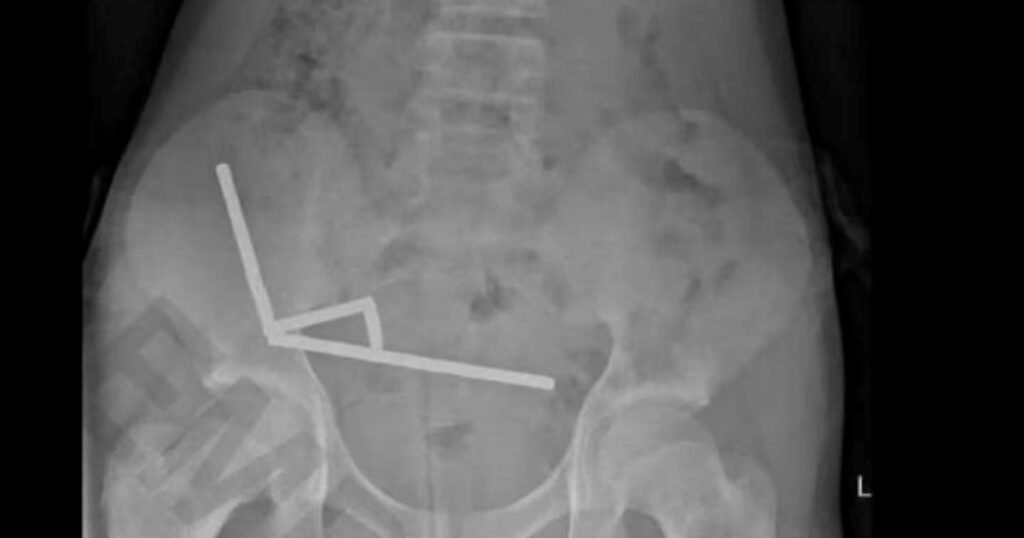

Un adolescente se tragó casi 200 imanes que compró por internet y perdió parte de su intestino

Los imanes más peligrosos del mercado se le unieron dentro del cuerpo.¿Qué son los imanes de neodimio y qué tan grave es su ingesta?